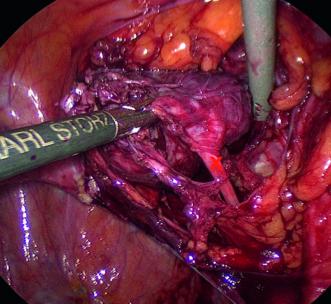

Eine 75-jährige Patientin wurde von ihrem Hausarzt bei rezidivierenden Harnwegsinfekten in die urogynäkologische Sprechstunde zugewiesen. Die Patientin berichtete, dass diese Beschwerden seit vielen Jahren bestünden und jeweils antibiotisch gut behandelbar waren. Die weitere Anamnese ergab, dass die Patientin zweimal per Spontangeburt geboren hatte und bei ihr vor gut 25 Jahren eine vaginale totale Hysterektomie bei Uterus myomatosus durchgeführt wurde. Seit einem ungewollten Gewichtsverlust von 4 kg vor ca. zwei Jahren sei ihr Gewicht immer stabil gewesen. Die Patientin bemerkte kein Fieber, keinen Nachtschweiss und auch keine Zunahme ihres Bauchumfangs. Bei der bimanuellen Palpation fiel eine indolente, prallelastische Resistenz in der rechten Adnexloge auf. Sonographisch stellte sich dieser Befund als polyzystische Raumforderung mit einer Grösse von 56 × 45 × 48 mm dar, welche teils verdickte Septen ohne vermehrte Durchblutung aufwies (Abb. 1). Die Tumormarker (CA-125 & HE-4) waren im Normbereich. Aufgrund dieses unklaren Adnex-Befundes wurde eine laparoskopische beidseitige Adnexektomie in die Wege geleitet.